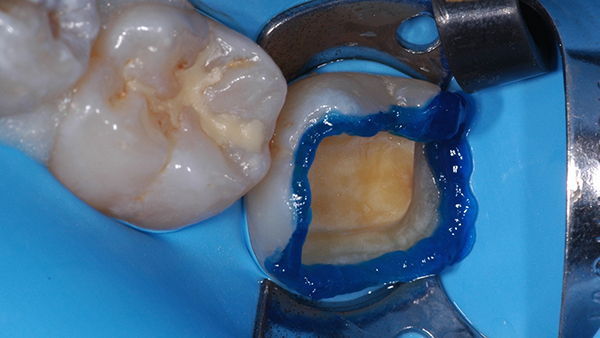

E' proposto alla paziente il piano di trattamento descritto e nel secondo appuntamento si è provveduto, previa anestesia tronculare del ramo mandibolare di destra, all'isolamento del campo operatorio mediante posizionamento della diga di gomma.

Si è proceduto attraverso frese diamantate sferiche e cilindriche ad alto-medio grit ( 107- 151 µm) montate su moltiplicatore di giri a rimuovere tutto lo smalto affetto da amelogenesi imperfetta e esporre il tessuto dentale normale.

Alla fine della procedura di preparazione dentale la cavità evidenzia ampie aree di dentina esposta ma altresì un contorno ben rappresentato di smalto sano e normale suscettibile al trattamento con procedure adesive smalto-dentinali.

La cavità si presenta abbastanza ampia e il restauro previsto dovrebbe ricostituire tutta la superficie masticatoria, le cuspidi di stampo vestibolari, la cresta inter prossimale distale e parte della cuspide disto-linguale.

Le procedure cliniche sono state indirizzate a isolare l'organo pulpo-dentinale mediante la messa in opera del sigillo immediato della dentina esposta "immediate dentin saling" ( 2 ) utilizzando allo scopo un sistema adesivo mild self-etch a due passaggi al quale ha fatto seguito foto polimerizzazione dello stesso secondo le indicazioni fornite dal fabbricante.